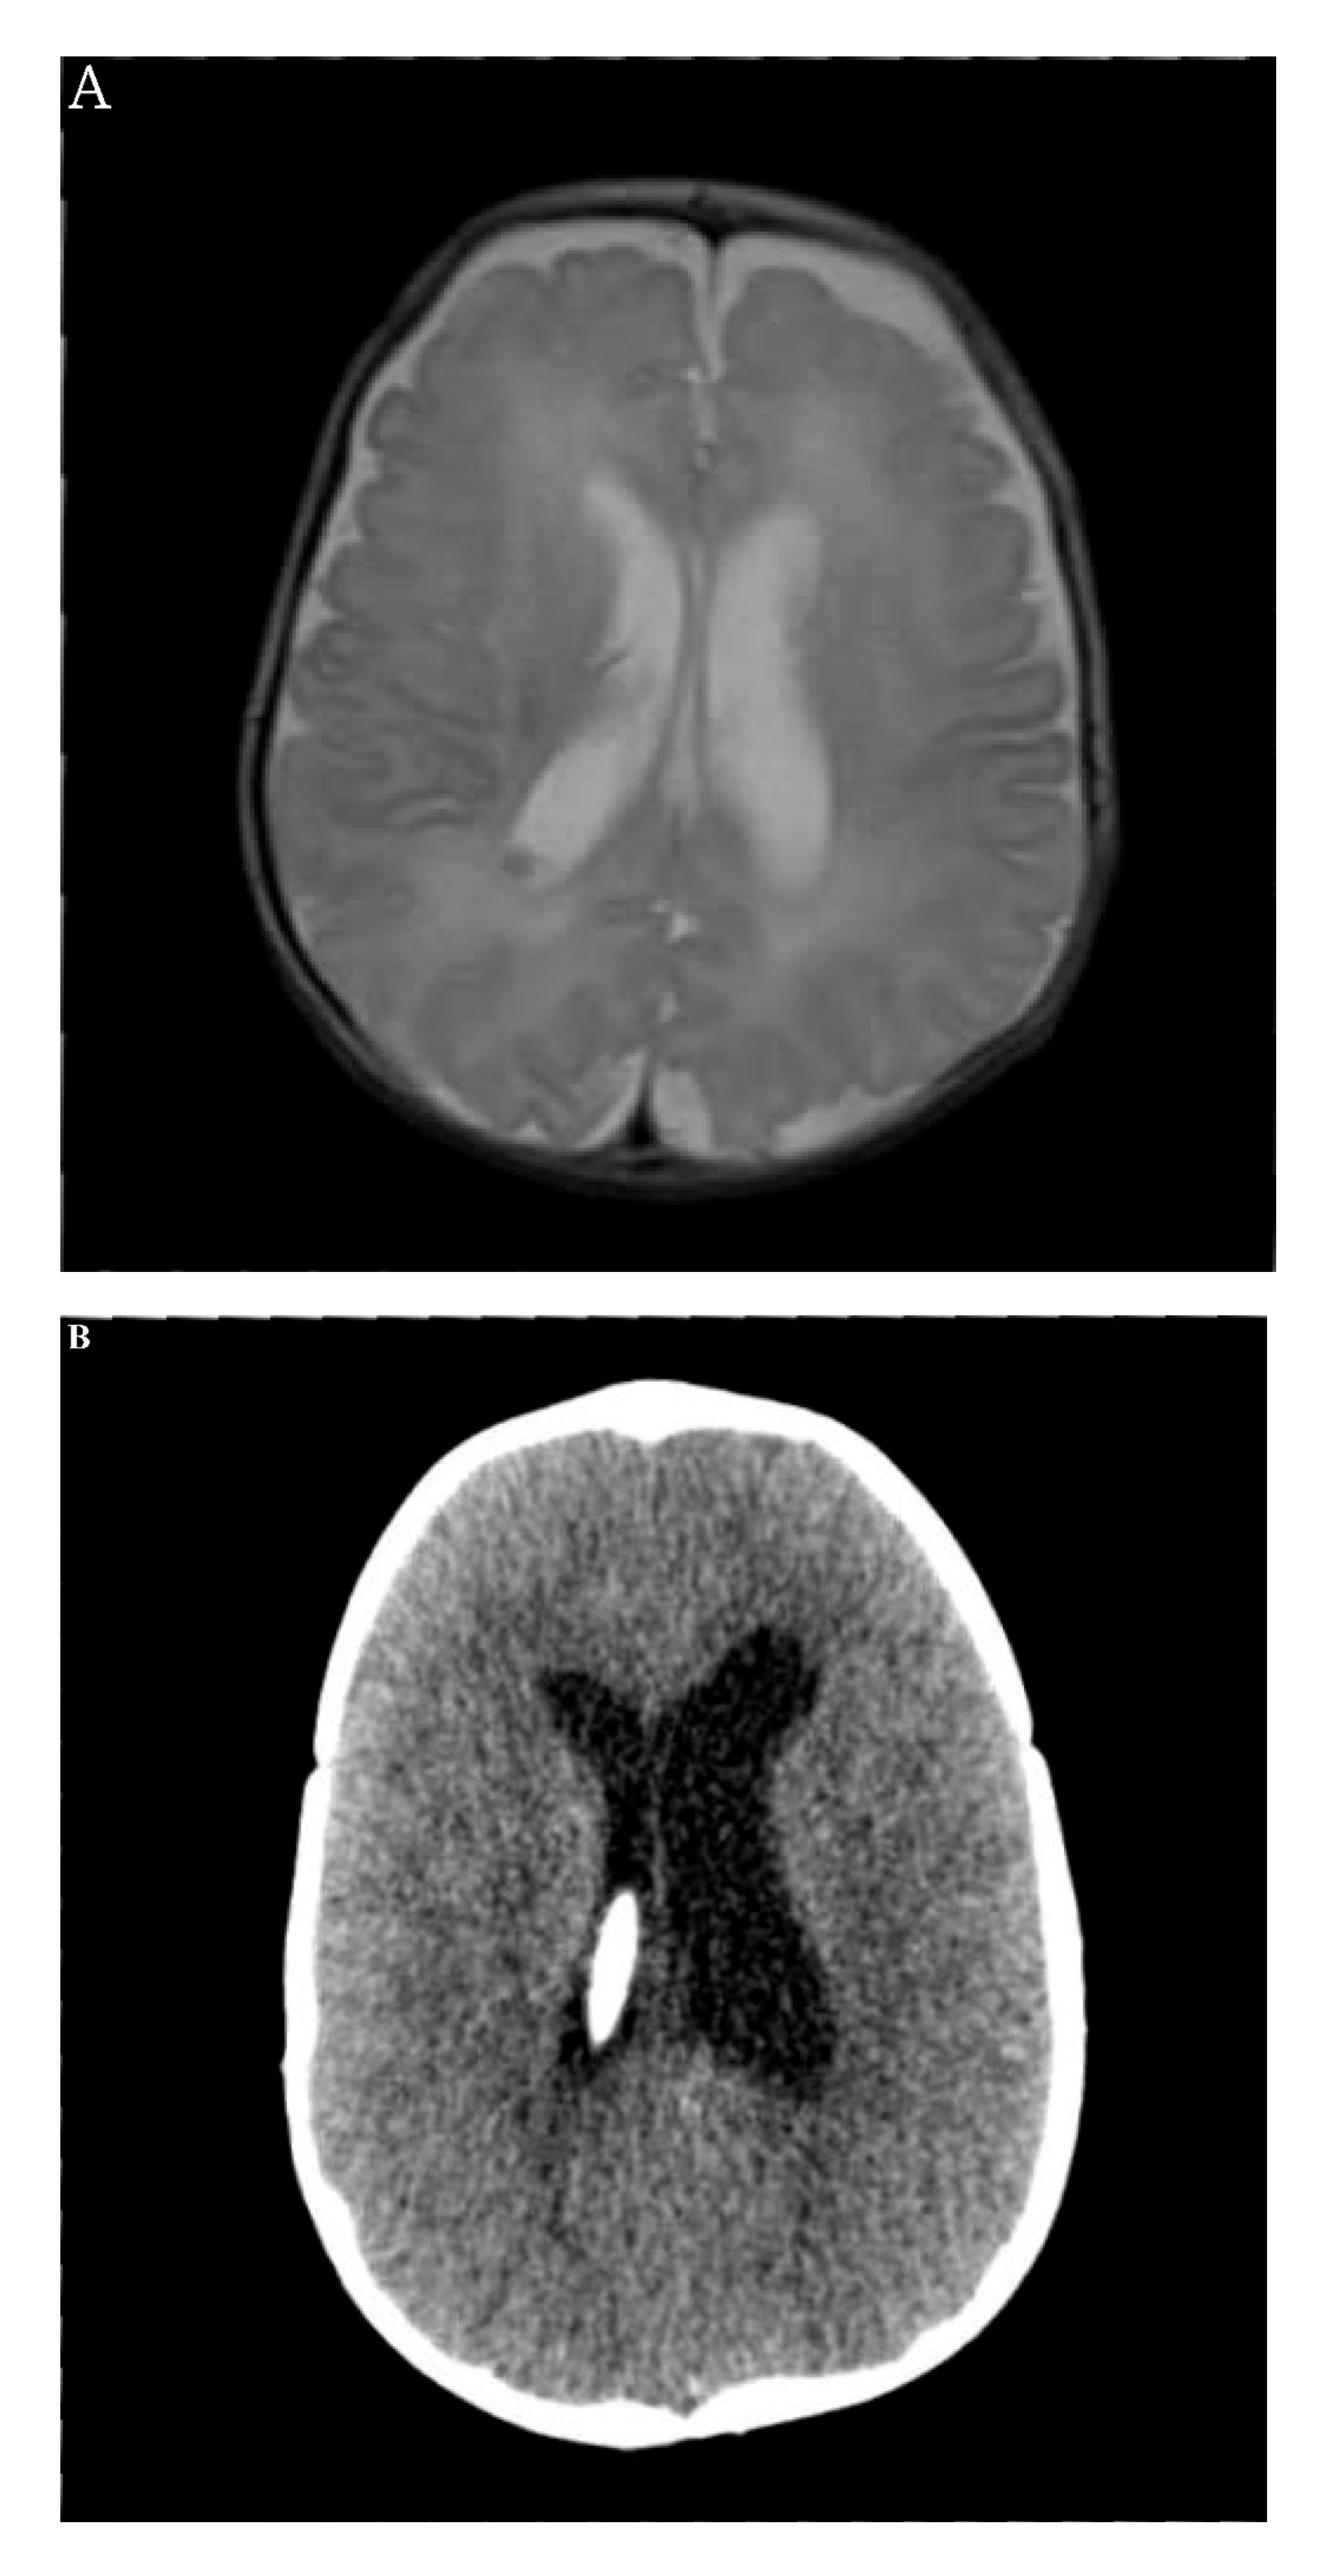

| Thyroid Function (Units) (Reference Range) | Ventriculomegaly | Bladder Stone | GDPP |

|---|---|---|---|

| T3 (ng/mL) (0.94–2.41) | 4.00 | 1.58 | 1.93 |

| fT4 (ng/dL) (0.80–2.00) | 3.76 | 1.40 | 0.94 |

| TSH (mIU/L) (0.60–8.00) | 0.06 | 0.09 | 0.01 |